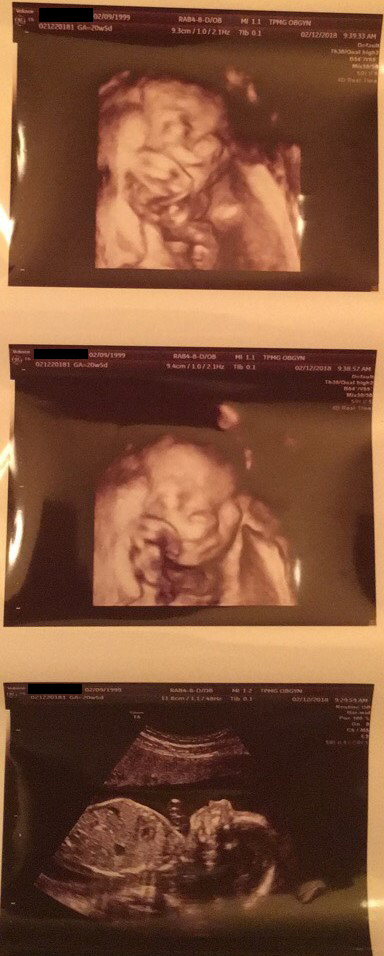

![]() |

| Ultrasounds of a 20-week-old baby |